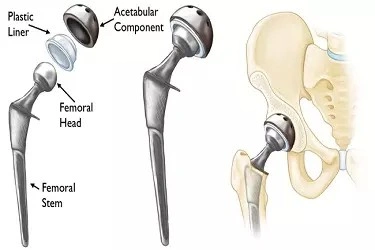

Hip replacement surgery involves replacing a damaged or worn-out hip joint with an artificial implant. This procedure is commonly recommended for patients suffering from severe joint pain or stiffness that does not respond to non-surgical treatments.

Modern hip replacement procedures are designed to provide long-lasting results while minimizing discomfort and recovery time.

Minimally invasive surgical methods may be used to reduce tissue damage and promote quicker healing. Advanced imaging systems help surgeons position implants correctly, ensuring optimal joint function.

With proper care and follow-up, hip replacement implants can provide durable results for many years.